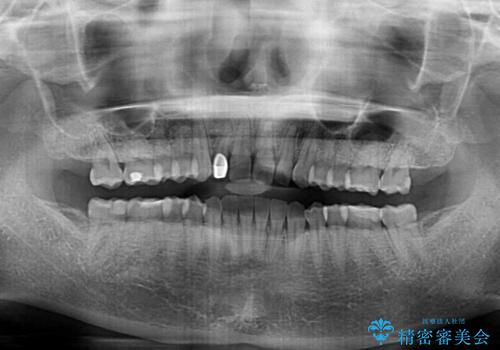

- 前歯の空隙と矮小歯を気にして来院された患者様です。

上下の歯列不正はインビザラインにより整えることとしました。

矯正治療の後に、前歯1歯と奥歯をオールセラミックにて治療することとしました。

矯正治療により矮小歯前後にスペースを作りながら歯列を整え、セラミッククラウン装着後に最終的に歯列と咬合を仕上げました。